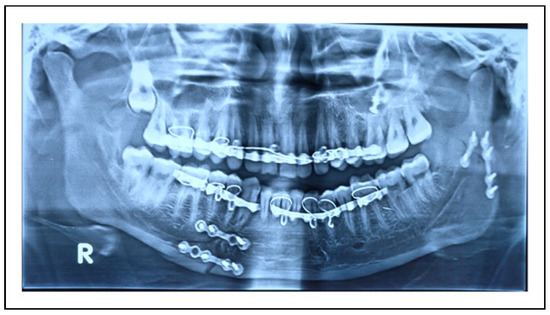

| Sr No. | Author, Publication Year & Country | Age Range | Male/Female | Two Miniplates Group | 3 D Plate Group | Parameters Assessed | Type of 3D Plate |

| 1. | Adhikari et al (2021) [14] India | 18+ years | 46/6 | 26 | 26 | 1. Intra-operative time taken for fixation 2. Ease of plate adaptation 3. Postoperative status of occlusion 4. Radiographic plate fracture 5. Maximum mouth opening 6. Protrusive, ipsilateral, and contralateral movements 7. Facial nerve status 8. Complications like development of a temporomandibular disorder, sialocele, infection, or hypertrophic scar. | Trapezoidal plate |

| 2. | Ahuja et al (2018) [15] India | 18 to 60 years | 17/3 | 10 | 10 | 1. Intra-operative time taken for fixation 2. Ease of plate adaptation 3. Postoperative status of occlusion 4. Need for intermaxillary Fixation 5. Maximum mouth opening 6. Lateral excursive and protrusive movements | Delta plate |

| 3. | Ganguly et al (2021) [16] India | 16+ years | 18/2 | 10 | 10 | 1. Complications like pain, wound dehiscence, infection 2. Mouth opening and lateral deviation while mouth opening 3. Biting efficiency 4. Need for postoperative intermaxillary fixation 5. Radiographic assessment of fracture reduction 6. Bite force | Delta plate |

| 4. | Rai et al (2021) [17] India | 21 to 59 years | 43/15 | 35 | 23 | 1. Occlusal stability 2. Postoperative complications like plate fracture, non-union, plate or screw loosening, plate or screw infection leading to implant removal, wound dehiscence, salivary fistula, and facial nerve paralysis. 3. Radiographic evaluation of fracture reduction | Rectangular plate |

| 5. | Scott et al (2020) [18] India | 18 to 53 years | 40/4 | 22 | 22 | 1. Time taken for fixation 2. Maximum mouth opening 3. Occlusal stability 4. Radiographic evaluation of fracture reduction 5. Jaw movements | Trapezoidal plate |

| 6. | Sehgal et al (2014) [19] India | 18 to 60 years | 26/4 | 15 | 15 | 1. Intraoperative assessment of reduction of fracture 2. Stability of occlusion 3. Need for intermaxillary fixation 4. Post-operative complications like tissue dehiscence and infection. 5. Bone Union 6. Plate Fracture | Rectangular plate |

| 7. | Sukegawa et al (2019) [20] Japan | Not reported | 16/10 | 14 | 12 | 1. Complications like postoperative infection, facial nerve paralysis, nonunion, malunion, and occlusal insufficiency, foreign body sensation by an osteosynthesis plate, and plate removal 2. Postoperative stability and occlusion | MatrixMANDIBLE subcondylar plate |